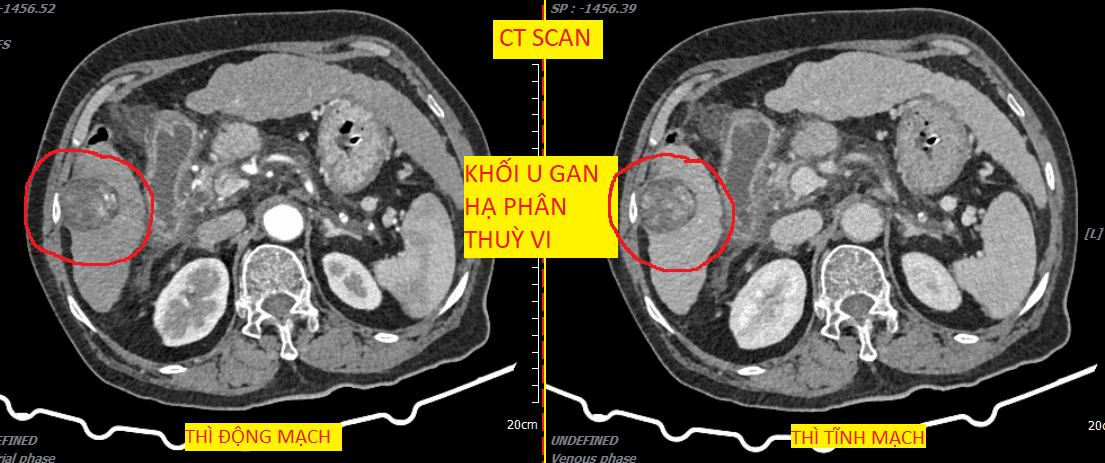

CT khối u gan.